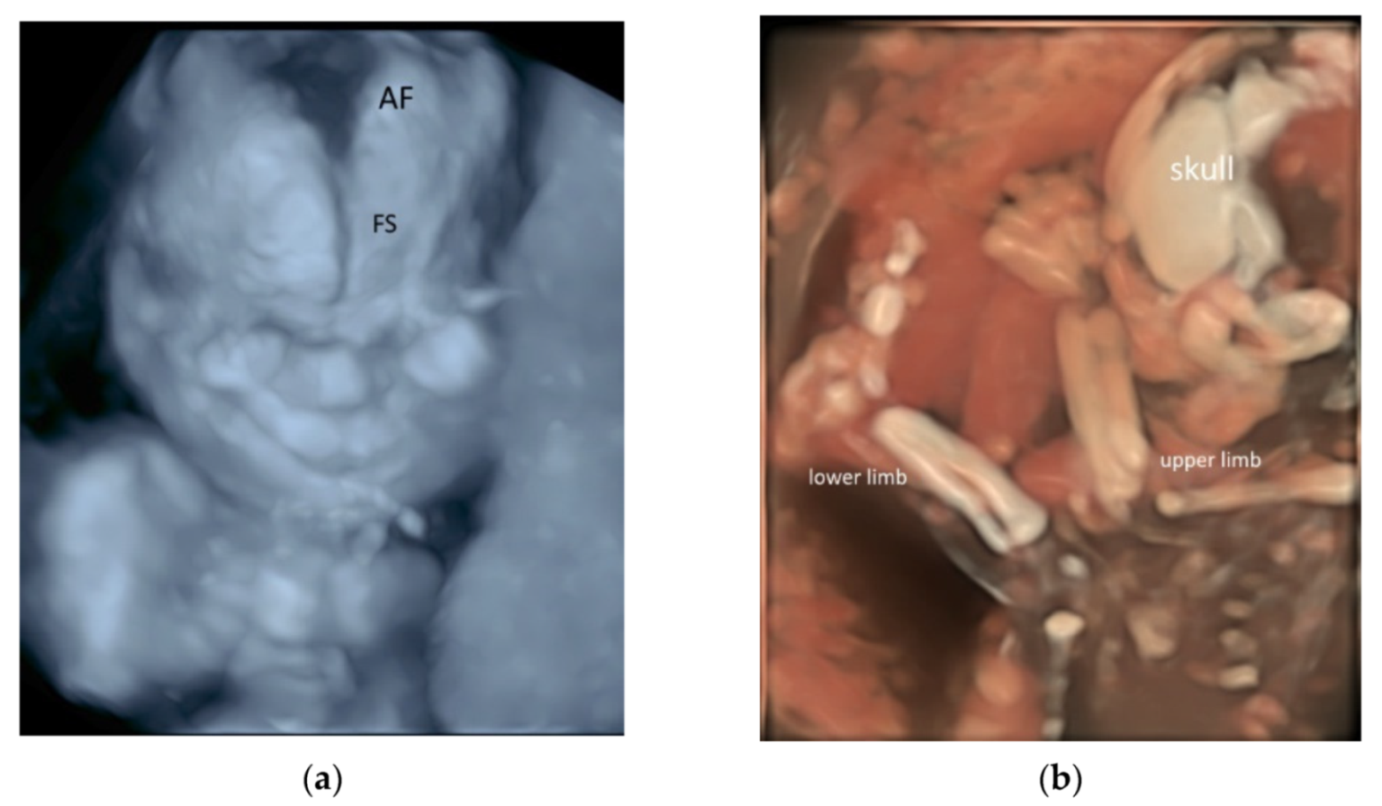

5. 3D/4D Ultrasound

5.3. 3D Ultrasound Examination of Face, Limbs, and Other Structures

- Tutschek, B.; Blaas, H.K. A human embryo in the palm of your hand. Ultrasound Obstet. Gynecol. 2017, 50, 539–540. [Google Scholar] [CrossRef] [Green Version]